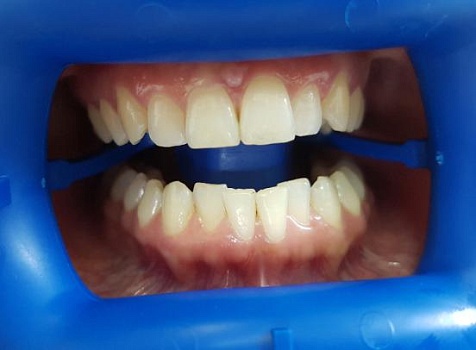

Изменения тканей, которые окружают корни зубов, к сожалению, неизбежны и с возрастом наблюдаются у всех, однако в разном объеме. Так, на развитие пародонтита влияет болезнетворная микрофлора полости рта, которая есть у каждого из нас, но на мы в силах повлиять на ее количество.

Сохранить зубы и пародонт помогает правильная гигиена полости рта дома и в кресле стоматолога, а также своевременное протезирование и имплантация, которые замещают удаленные зубы и равномерно распределяют жевательную нагрузку, не позволяя костной ткани атрофироваться.

Таким образом, по мнению стоматологов, риск возникновения болезней десен на 80% зависит от сознательности самого пациента.